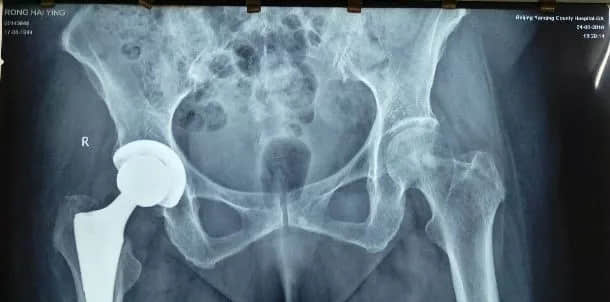

股骨头坏死要尽快置换

人工关节的使用寿命根据材料、手术技术和病人个体情况,会有不同的差异。通常假体生存率15年的病人可以达到95%左右,20年的假体生存率可以达到90%。

也有采用耐磨产品,如陶瓷对陶瓷等,它的设计使用寿命是按30年来计算的,当然能否达到这个时间,还要看个体骨质和使用习惯。

因此做人工关节建议的年龄为60岁以上。但低于60岁的患者如果关节疾病严重,影响患者日常生活,为提高患者的生活质量也可以接受置换手术。

股骨头坏死的每一阶段都有相对应的保守、保髋和置换等治疗方法,而全髋置换是对股骨头坏死晚期患者才会主张应用的治疗方案。

当然中青年晚期患者做人工关节置换,日后可能会面临翻修手术,需要有心理准备。